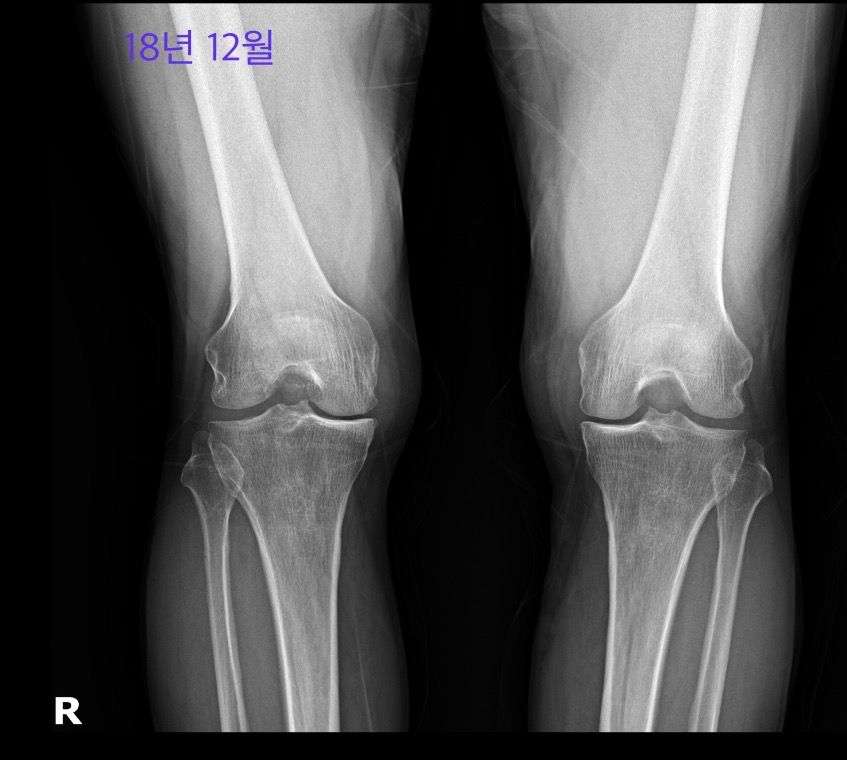

사진은 18년 5월, 18년 12월, 24년 5월입니다.

• 2번 째 사진

우측 무릎은 18년 5월부터 이미 진행이 많이 되어있는 상태이고 18년 12월에는 관절간격이 조금 더 넓은것처럼 보이지만 현재 grade 4로 보입니다.

좌측은 18년 5월에 우측보다는 가볍지만 grade 3이라고 생각되며 현재 grade 3-4 정도로 보입니다.